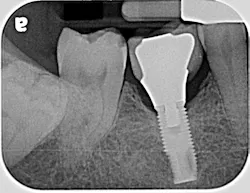

If the occlusal forces delivered to the implant-abutment-crown complex exceed the screw’s clamping ability, this may result in either its loosening (figures 1a and 1b) or, in more severe situations, fracturing of the screw (figures 2a–2c). Clinicians often indite the occlusion as being the primary culprit for the problem; however, in a number of instances, this may not be the case. The cause of screw loosening could also be due to using aftermarket parts, which do not have the precise fit of those made by the manufacturer of the implant.7